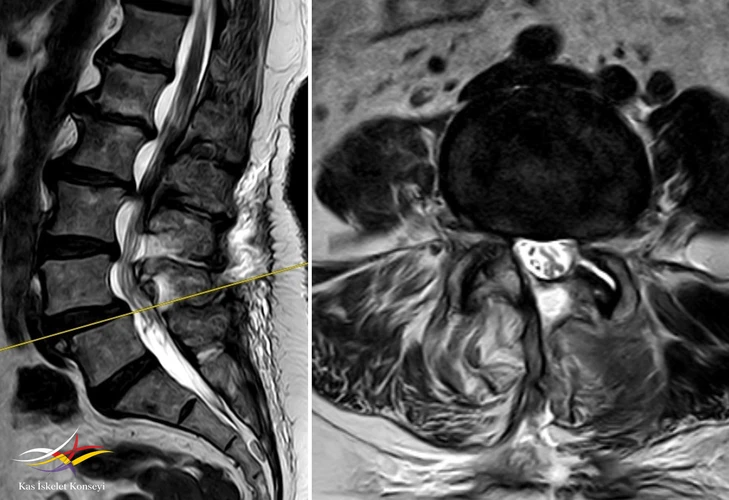

Resim 8. L4-5 seviyesindeki dekompresyon görülmekte.